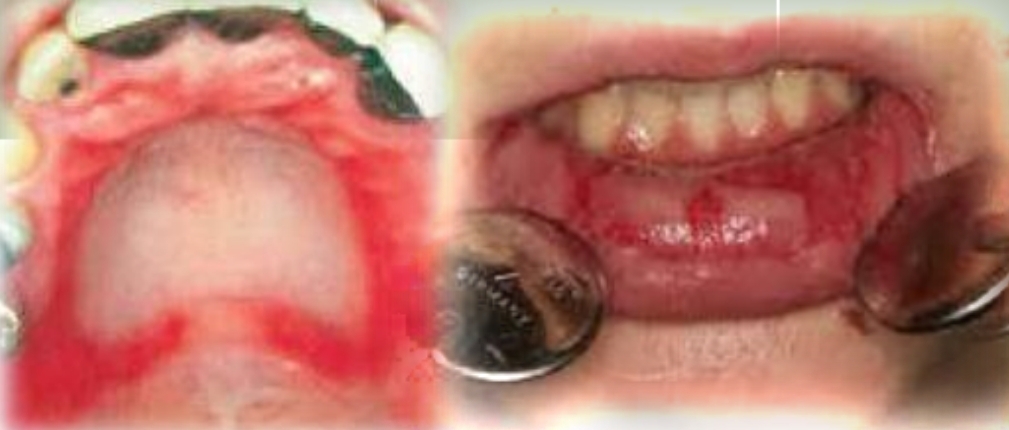

Widespread and painful, red macules, vesicles, bullae and ulcers. Blood crusted lesions on lips. Target lesions on skin.

Acute onset, fever, malaise

Second decade

Male prediliction

Found on:

Oral lesions: Lips, tongue, buccal mucosa, soft palate

Skin ‘Target’ lesions on: Extremities and head and neck region

Erythema multiforme

Common precipitating factors:

HSV

Medications

Major and minor forms exist

Treatment - Withdrawl of medication, lubricate lips, symptomatic relief. Hospitalization of severe. Reccurences common if triggered by HSV

DD - Primary herpetic gingivostomatitis, Necrotizing ulcerative gingivitis, Apthous major ulcers, Chemical burn